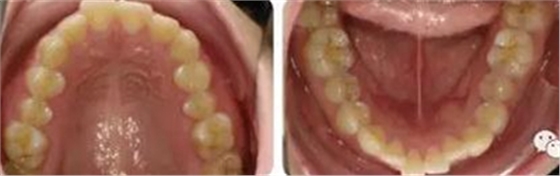

上下牙列輕度擁擠,牙弓偏尖圓形;前牙深覆合深覆蓋;雙側(cè)磨牙尖牙偏遠(yuǎn)中關(guān)系。

曲斷顯示38、48阻生;雙側(cè)TMJ髁突頭略不對(duì)稱(chēng)。